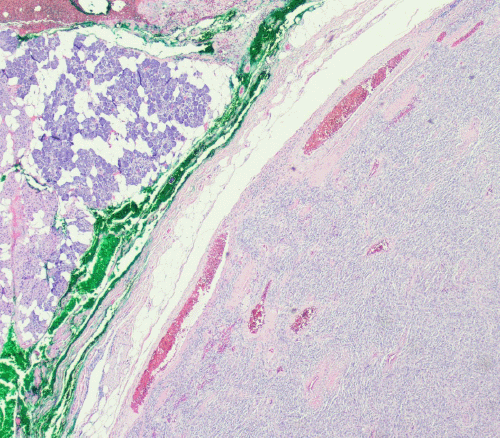

In this case, the initial fine-needle aspiration (FNA) biopsy performed in the office revealed cellular atypia of undetermined significance. FNA findings typically consistent with SFT would include oval or spindle-shaped cells, often arranged in irregular clusters, within a background of irregular collagen fragments. The non-diagnostic FNA result prompted a discussion with the patient regarding options, including repeat FNA versus excisional biopsy for definitive diagnosis, leading to her consent for the superficial parotidectomy. Grossly, the excised mass was described as a tan-to-white, partially encapsulated, firm lesion with well-circumscribed borders, consistent with the macroscopic appearance of other parotid SFTs reported in the literature. Histologically, SFTs often exhibit a “patternless” architecture of ovoid or spindle-shaped cells with high vascularity, although significant histological variability can exist.9 These characteristic features were observed in the tumor resected from this patient (Figures 2-4).

Figure 2. Low-Power Histopathology of Parotid Solitary Fibrous Tumor. Published with Permission

H&E stain, 5x original magnification of the resected parotid tumor. The image shows benign salivary gland acini and adipose tissue (left side of field) adjacent to the spindle cell lesion (right side of field), which exhibits a circumscribed, “pushing” border against the normal parotid parenchyma